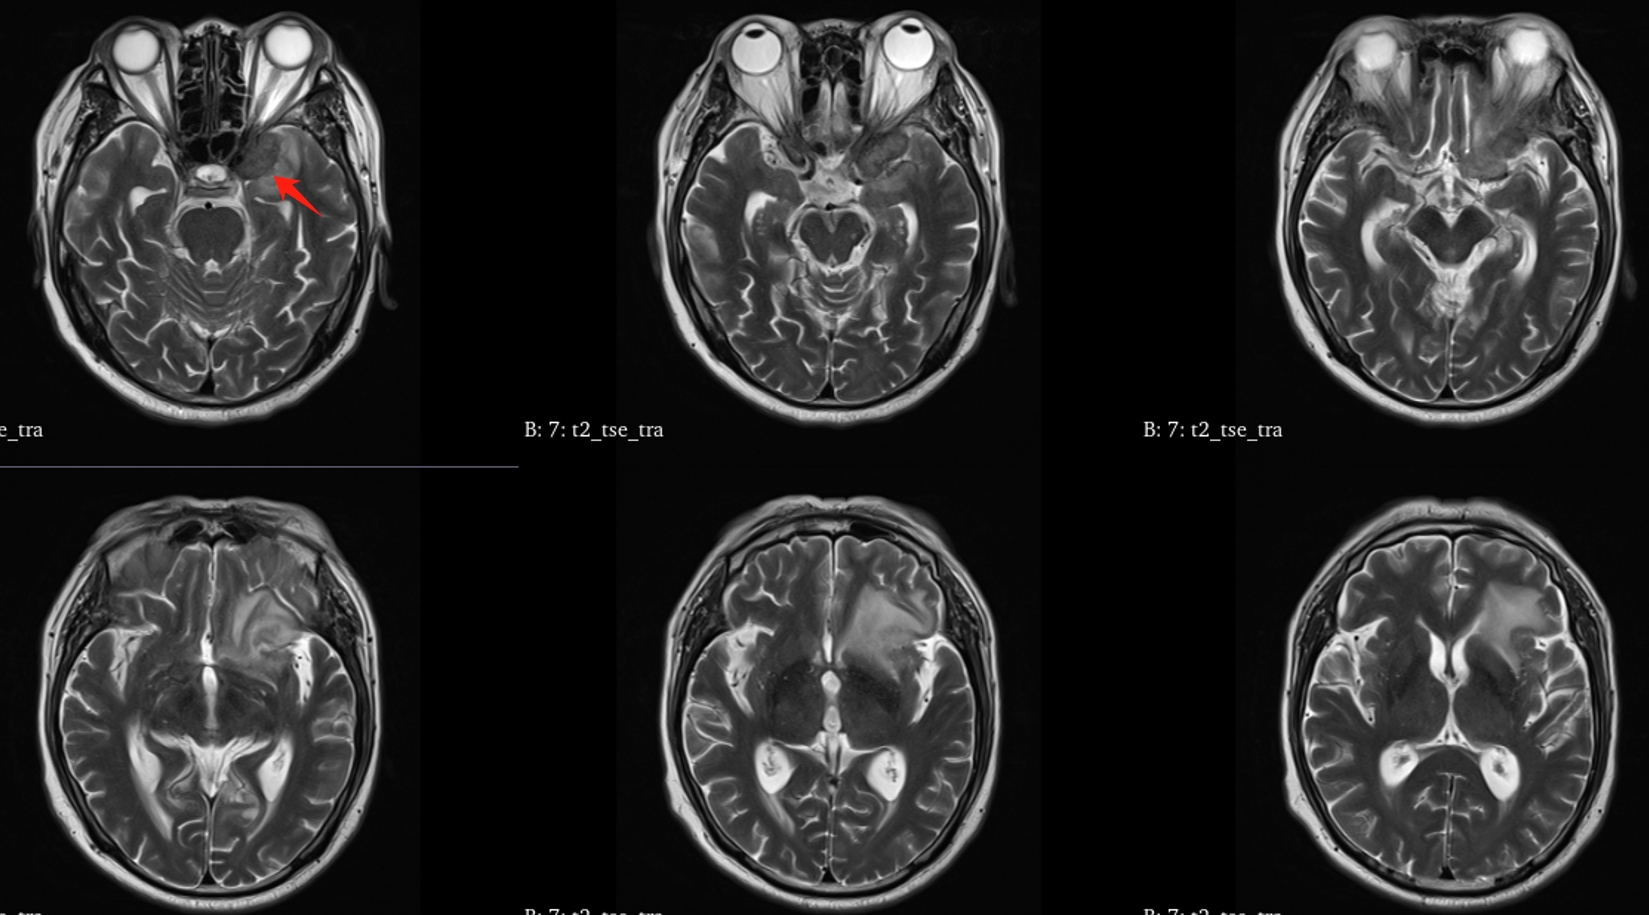

该患者入院后完善常规颅脑影像学检查,左侧颞叶病变,疾病性质不详,转移瘤、胶质瘤、炎症类疾病均不能排除,遂行PET-CT检查,提示左侧颞叶高代谢,淋巴瘤不能排除。组织MDT会诊建议可先行腰椎穿刺查脑脊液脱落细胞学、感染指标,若仍不能确诊,可进一步行开颅病灶切除,术中快速冰冻,根据冰冻结果决定手术手术策略。患者脑脊液脱落细胞学结果:较多淋巴细胞,少许单核细胞及个别中性粒细胞,未见异形细胞,脑脊液常规、生化、脑脊液培养未见细菌生长,诊断仍不能明确,且患者病情进展迅速,患者神志呈昏睡状态,颅脑MRI提示病变较前明显增大(影像学检查间隔两周),且水肿明显加重,遂行开颅病变切除术。术中见部分病变累及蝶骨嵴硬膜,病变质地硬韧,内有多个囊腔,囊内容物为黄色粘稠样脓性物质,留取囊液及实性部分送快速冰冻,在等待冰冻过程中,进一步探查见肿瘤侵犯左侧颞叶,该部位肿瘤质地相对软,无包膜,与周围脑组织无边界,血运不丰富,内有多个囊腔,且肿瘤侵犯侧裂池、颈动脉池,左侧视神经、颈内动脉、大脑中动脉均被病变包绕,且该处肿瘤质地偏硬韧。术中快速冰冻提示组织大片变性坏死,伴胶质增生及淋巴增生。结合病变质地及冰冻结果,考虑为非肿瘤性疾病,可能为炎性病变伴肉芽肿形成可能性大,且肿瘤质地硬韧,累及范围广泛,难以全切,遂行肿瘤大部分切除后结束手术。术后病理结果明确后予以伏立康唑、醋酸卡泊芬净抗真菌治疗。在治疗过程中患者先后出现脑出血、脑梗塞,最终因治疗周期长,花费高、效果不确定等因素,家属放弃治疗,于术后1月去世。

GM实验,GM是曲霉菌细胞壁的主要成分,是疾病早期释放至体液中的抗原之一。据报道,脑脊液GM试验诊断ICA的敏感度及特异度分别为88.2%及96.3%,且阳性预测值及阴性预测值均超过90%,脑脊液GM水平与曲霉菌感染严重程度相关,监测该指标可评价治疗效果及预后。影像学检查具有多样性,多为反复慢性炎症、肉芽肿样改变,部分易累及颅底。

目前确诊ICA仍依赖于病灶切除或活检,获得组织病理学、直接镜检或培养证据。《颅内曲霉菌病诊治中国专家共识》推荐:当临床症状怀疑ICA时,应尽早行脑脊液检查(常规、生化、培养、G试验、GM试验及mNGS)及颅脑MRI平扫+增强检查。怀疑窦源性ICA时,还应加做颅底CT检查。当临床症状符合ICA,但上述检查结果为阴性时,可重复送检。条件允许时,及时行标本镜检与培养获得确切证据。尤其是对于长期应用激素、免疫功能缺陷高危患者。